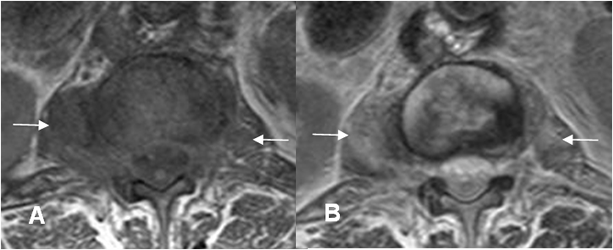

Fig 147 D. Espondilodisquitis TBC. Igual paciente anterior.

A: RM axial en T1 simple y B: RM axial en T1 con contraste. Cambios inflamatorios en el cuerpo vertebral, con masas de tejidos blandos paravertebral, las cuales realzan con el contraste, por espondilodisquitis TBC. No hay compromiso del saco dural.